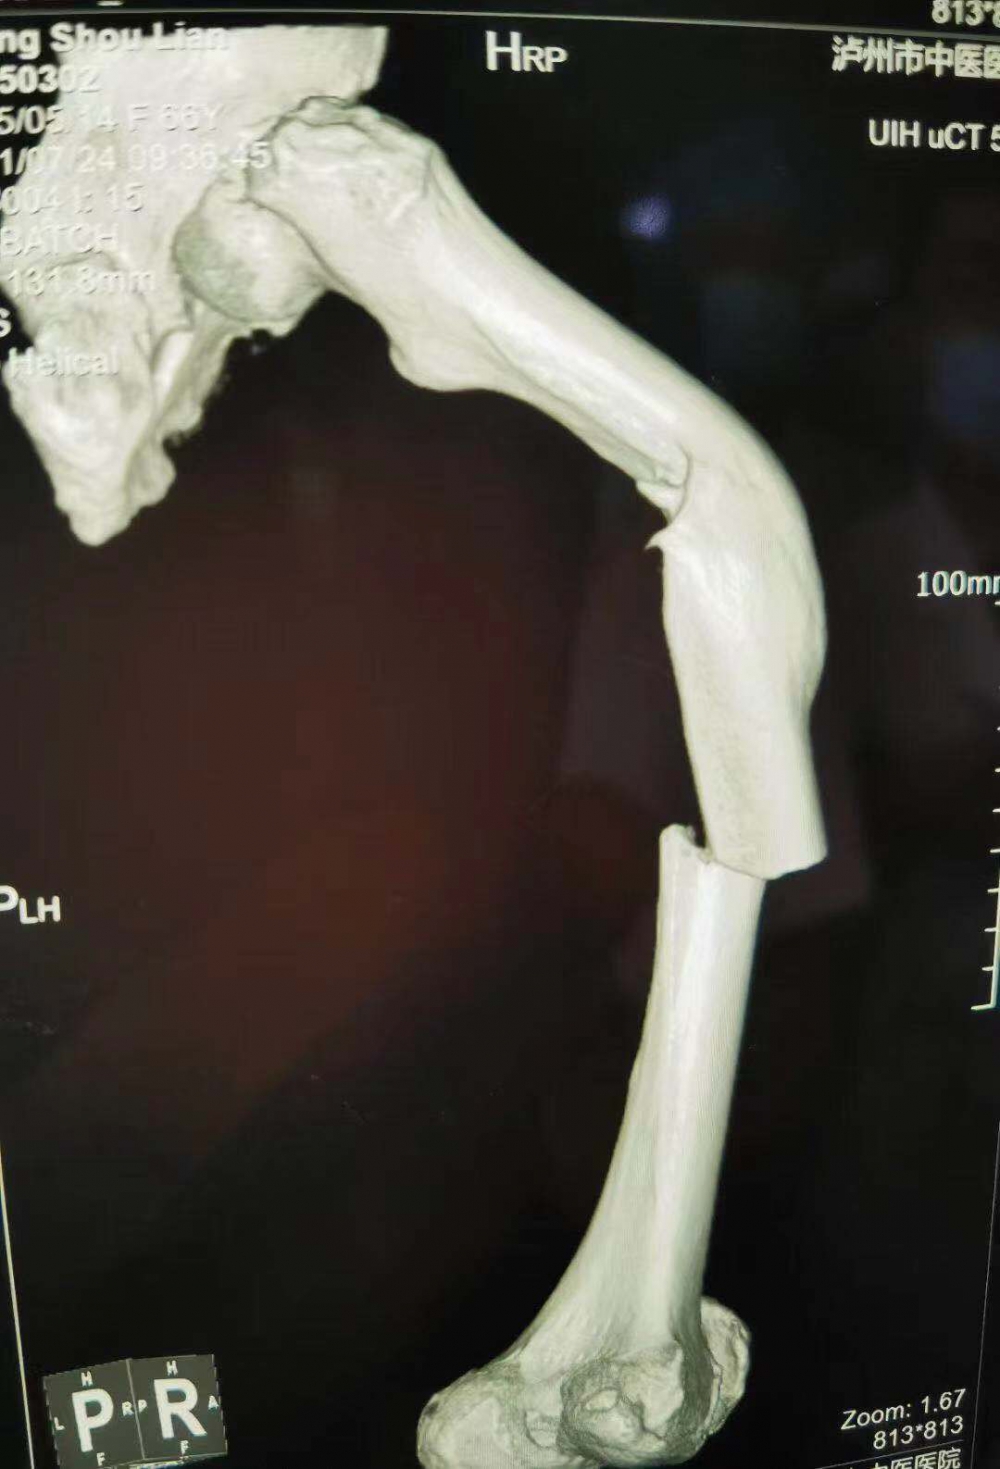

(股骨中段断裂,上端有明显畸形)

当她的X光片出来时,收治的医生都被她的伤情吓了一跳。原来此次她骨折的上端还有一处骨伤畸形愈合。这是什么情况呢?

原来张守莲在三年前还摔伤过一次,当时在一家医院进行了手法复位,但因操作不当,没能复位成功,留下了后遗症。三年来她都是以拄拐行走。